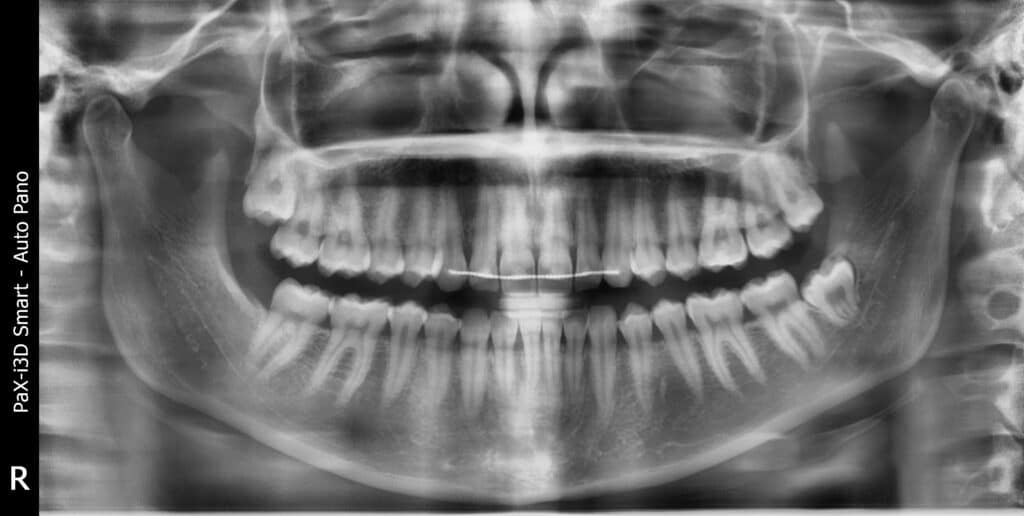

Az intraorális röntgen a leggyakoribb típusú fogászati röntgen. Az „intraorális” szó azt jelenti, hogy szájon belüli, ami itt arra utal, hogy a röntgenfelvételek a száj belsejébe helyezett készülék segítségével készülnek el.

Az eljárás egy, vagy pár fog rendkívül részletes feltérképezését teszi lehetővé, pontosan megmutatva az üregeket, a gyökereket, a csontszinteket és a környező szöveteket stb.

Az intraorális röntgenfelvételeknek több típusa is létezik, így érdemes megemlíteni

- a bitewing röntgenfelvételeket, amelyek a felső és alsó fogak koronáit együtt mutatják (jól alkalmazható a fogak közötti üregek és a csontvesztés kimutatására),

- a periapikális röntgenfelvételeket, amelyek a teljes fogat mutatják a koronától a gyökércsúcsig (jól alkalmazható fertőzések, tályogok, gyökérproblémák esetén), valamint

- az occlusalis röntgenfelvételeket, amelyek az állkapocs egy részének nagyobb képét mutatják (alkalmasak beékelődött fogak, többletfogak, állkapocs fejlődésének vizsgálatára stb.).